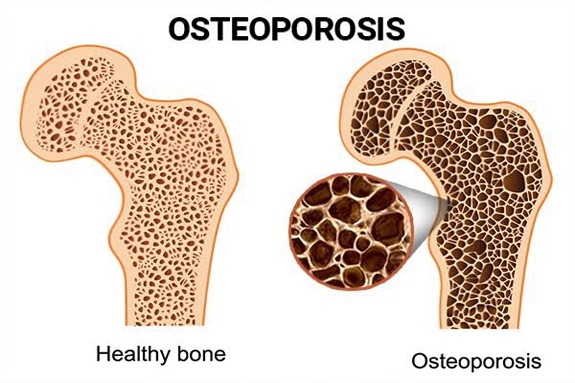

Osteoporosis